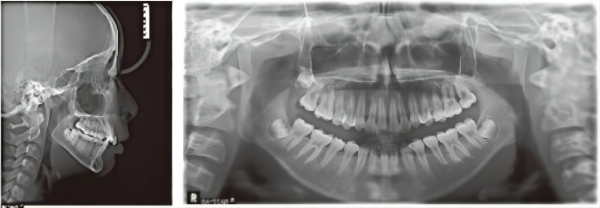

X-ray

Moderate crowding in the maxilla, mild crowding in the mandible, congenital absence of tooth 41, deep overbite and overjet, 24 and 25 being scissor bite with 34 and 35, bolton discrepancy in the anterior teeth, poor oral hygiene. Maxillary molar distalization with appropriate IPR, narrowing the maxillary arch and expanding the mandibular arch, Class II traction to establish a good posterior relationship with cusp-to-fossa occlusion and normal overbite and overjet of the anterior teeth, treatment duration of 2.5 years.